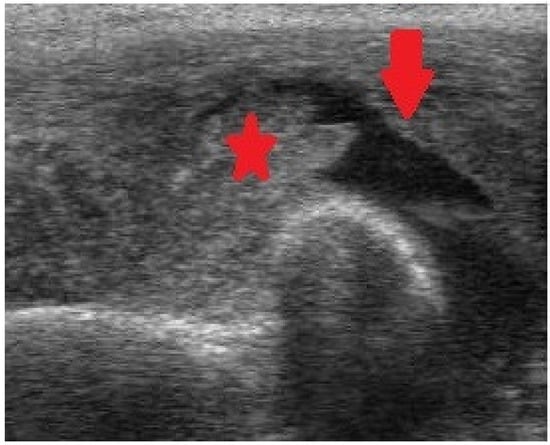

Figure 4.

Ultrasonography (US) of the elbow exhibiting intraarticular fluid (arrow) and intense synovial enlargement (asterisk).